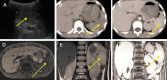

Hamartomas are extremely rare splenic benign tumours in children. We present two cases, both in boys (6 and 8 years old), with left upper quadrant abdominal pain that were otherwise asymptomatic. Both patients showed a splenic mass on preoperative ultrasonography and magnetic resonance imaging (MRI). One patient had a focal splenic mass that was identified preoperatively with contrasted computed tomography (CT) scans. Both patients underwent a total splenectomy. Although multi-modality imaging findings were described preoperatively, the final diagnosis in each case was splenic hamartoma based on histology and immunohistochemistry. The postoperative courses were uneventful.